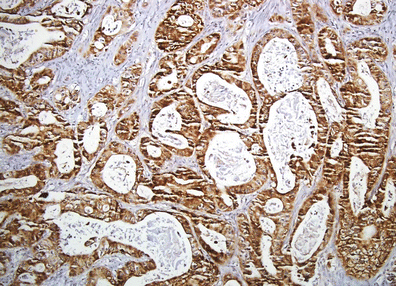

CRABP I expression in the cell cytoplasm of pNET G2 (Ki-67–9 %).: